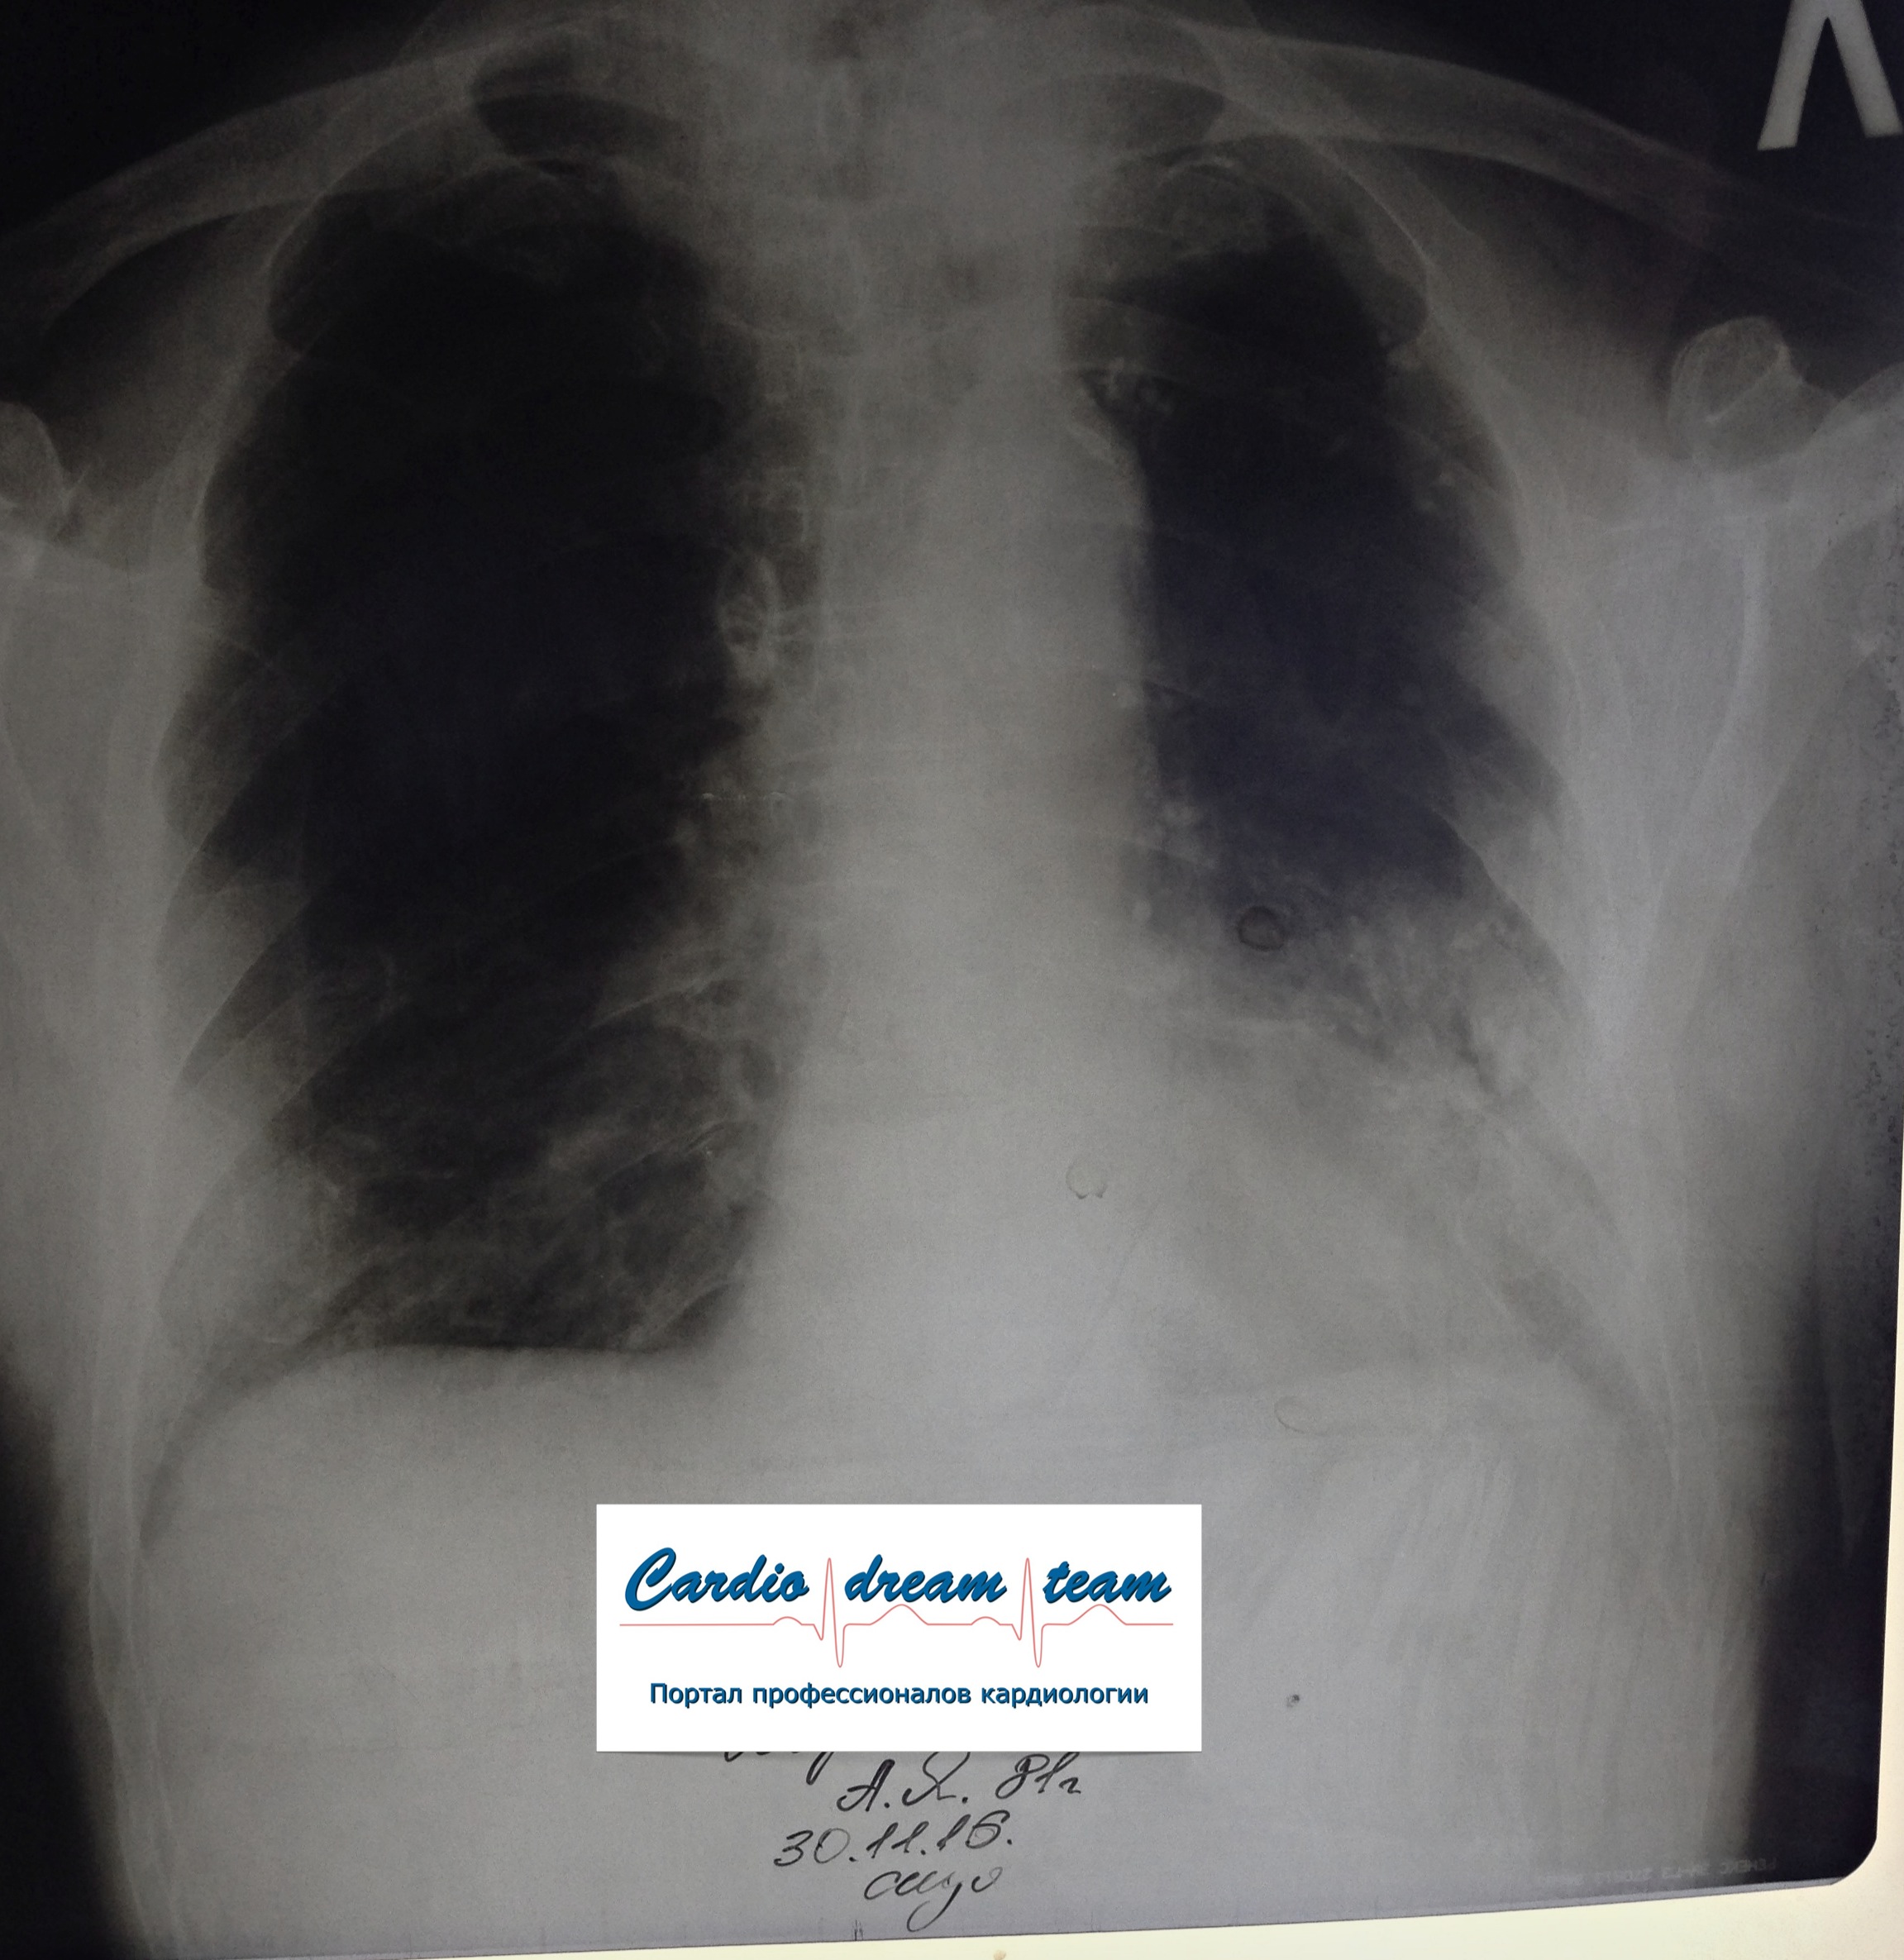

Не обсуждалась Дата 23-ИЮЛ-15 ОПИСАНИЕ: Проведена рентгенография органов грудной клетки в прямой проекции, положение лежа, условия ПИТ Легочные поля: неравномерно прозрачны за счет сосудистого обогащения, в базальных отделах с обеих сторон, отмечается сгущение легочного рисунка, за счет гиповентиляции, в плевральных полостях жидкость Легочный рисунок: Изменен по смешанному типу: обогащен за счет сосудистого компонента, деформирован за счет склероза. Корни: бесструктурны, расширены за счет сосудистого компонента, обогащены Синусы: определяется наличие жидкости по линии 5 ребра Сердце: широко лежит на диафрагме отмечается расширение границ сердечной тени влево, вправо экг-электроды. ЗАКЛЮЧЕНИЕ: Рентген-признаки 2-х стороннего гидроторакса с гиповентиляцией базальных сегментов.. Признаки застоя по МКК 2 степени (умеренно выраженный). Пневмосклероз. Р-признаки гипертрофии левого желудочка сердца. Склероз аорты.